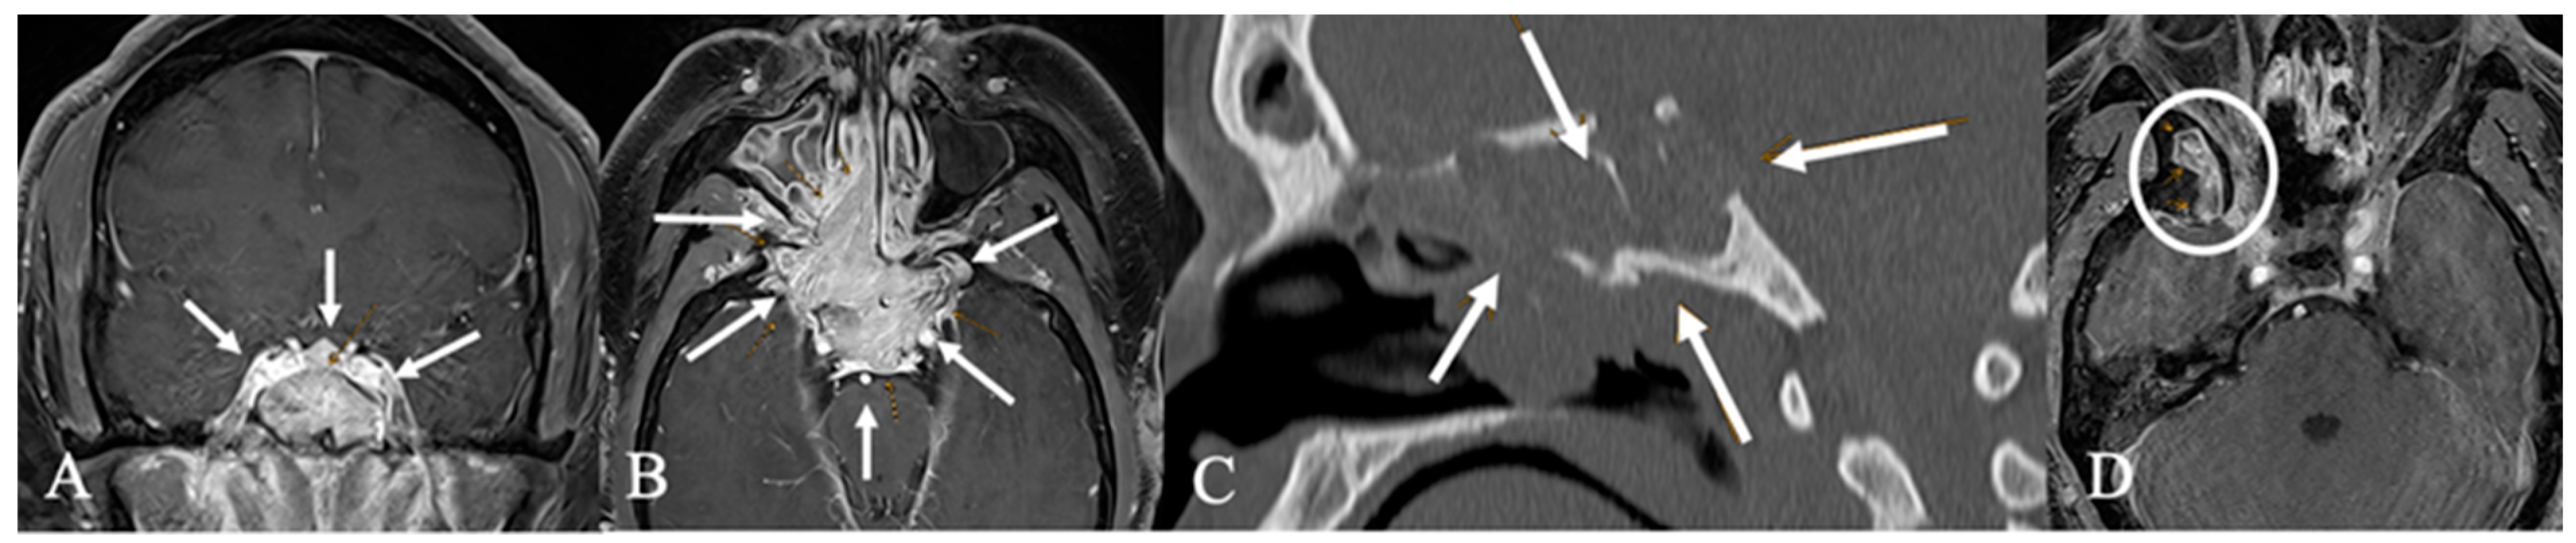

3.3. Imaging Characteristics

| MRI | CT | ||||

|---|---|---|---|---|---|

| Tumor Entity % (n) | Contrast enhancement % (n) | Infundibulum % (n) | Chiasma % (n) | Bone destruction % (n) | Sphenoid sinus infiltration % (n) |

| Dysontogenetic tumors 64% (30) | 43% (13) inhomogeneous 47% (14) marginal | 20% (6) infiltrated | 37% (11) contact 13% (4) compression | 10% (3) osteolytic 7% (2) infiltrated | 17% (5) |

| Pituicytoma 2% (1) | 100% (1) homogeneous | 100% (1) infiltrated | 100% (1) compression | ||

| Metastasis 9% (4) | 75% (3) inhomogeneous 25% (1) homogeneous | 75% (3) infiltrated | 75% (3) compression | 75% (3) osteolytic | 75% (3) |

| Vascular 2% (1) | 100% (1) inhomogeneous | 100% (1) infiltrated | 100% (1) contact | ||

| GII 9% (4) | 25% (1) inhomogeneous 50% (2) homogeneous 25% (1) marginal | 25% (1) infiltrated | 75% (3) contact 25% (1) compression | 25% (1) osteolytic | 25% (1) |

| Carcinoma 6% (3) | 33% (1) inhomogeneous 67% (2) homogeneous | 100% (1) infiltrated | 66% (2) | ||

| Germinoma 2% (1) | 100% (1) inhomogeneous | 100% (1) infiltrated | 100% (1) compression | ||

| Others: 6% (3) | 100% (3) inhomogeneous | 33% (1) infiltrated | 66% (2) osteolytic | 66% (2) | |

| Total: 100% (47) | |||||